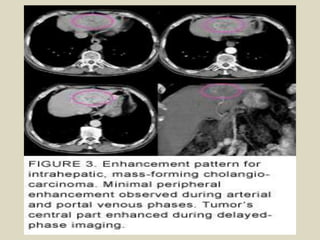

Intrahepatic cholangiocarcinoma About 20% to 30% of

cholangiocarcinomas are peripheral intrahepatic masses.

These masses often appear similar to metastases, and can

easily be misdiagnosed as adenocarcinoma metastases of

unknown primary. Sonographically these masses may have

mixed echogenicity, or predominantly hypoechogenicity or

hyperechogenicity, depending on the predominant underlying

stroma, fibrous tissues versus mucin producing glandular

material. CT and MR appearances are often nonspecific. The

tumors are of lesser attenuation than liver on unenhanced CT

and have a variable enhancement pattern: usually not strongly

enhancing during arterial phases of enhancement, but

showing patchy and usually peripheral enhancement that may

start mildly during the arterial contrast phase and become

more prominent during the portal venous phase.

Intrahepatic cholangiocarcinoma.